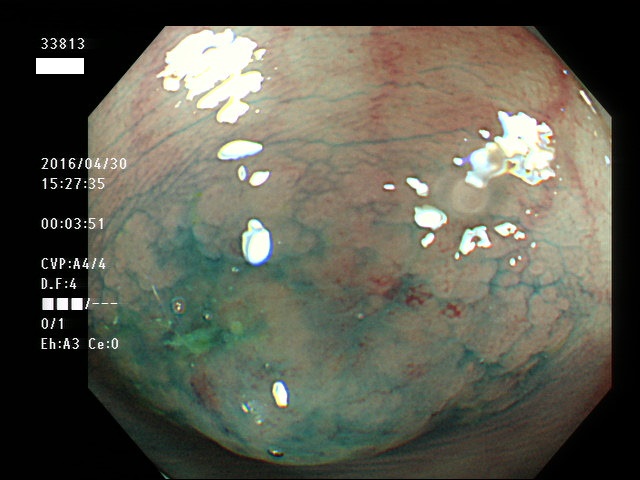

上記100名より抽出した平坦・陥凹型腺腫(=癌化の危険が高いが見落としやすい病変)の内視鏡写真